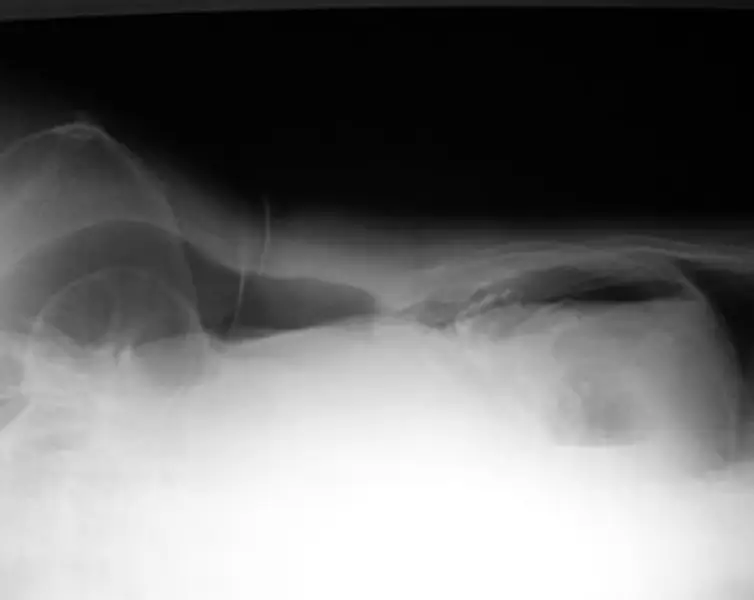

80 歲女性為長期糖尿病、高血壓及中風不良於行之病人,因急性腹痛來急診就醫,其平躺之腹部 X 光如圖 (一),另一張左側躺之腹部 X 光檢查如圖 (二),下列敘述何者正確?

Left lateral decubitus 腹部 X 光(圖二):

- 患者左側臥,空氣自然上浮至右側非依賴區(即肝臟與腹壁之間),形成明顯半月形放射透亮影。

- 可清楚見 free air 輪廓與肝下緣之間的分界,為診斷游離氣體最直接的證據。

→ 左側